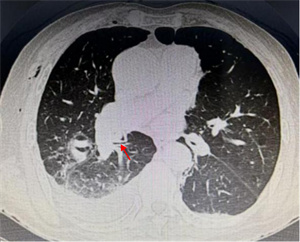

10月18日夜间急诊,来了一位14岁小患者,他在将手表零件放口中玩耍时,不慎吸入气管内。气管内异物是十分危急的,随时可能危及生命。小患者自觉胸闷不适,不时有咳嗽。急诊胸片和CT可以清晰地显示位于右中叶内侧段一长约2.3cm针形异物,两端较尖,急诊科医生程争启紧急联系呼吸与危重症医学科会诊,白克林主任考虑金属异物锐利可能损伤肺内血管造成大出血,准备急诊行内镜取异物。疼痛科、内镜室医务人员迅速反应,立即从家中赶往医院,争分夺秒做好各种术前准备工作。

鲜美的动物骨髓深受很多人喜爱。一位中年患者清晨急匆匆来到我院呼吸科住院部。主诉前一天晚餐吸食猪骨髓时,不慎将食物吸入气管,出现反复剧烈咳嗽,并有咯血。我院呼吸科医生在其急诊胸部CT中发现右中间段支气管有一 “刀片样异物” 横在管腔内。评估病情并做好预案后,医生顺利取出一锐利骨片异物,有效阻止了 “利器” 造成肺内出血恶果的发生。